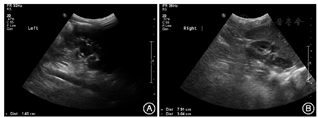

当地和本院辅助检查:血尿常规、肝肾功能、离子类、血气分析、电解质、甲状腺功能、TORCH、尿GC/MS遗传代谢筛查均正常范围或阴性。腹部超声显示左肾集合系统分离1.5 cm,左肾9.3 cm×4.5 cm;右肾形态偏小,为7.9 cm×3.0 cm(图2)。头颅CT示丘脑有小钙化灶。X线检查未见胸部明显异常或异位胸腺。头部肿块当地活检病理结果提示为"皮脂腺瘤"(未见具体病理报告)。